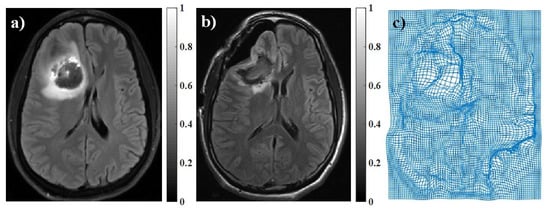

2.2. Murine Brain Data

2.3. Inducing Brain Deformation